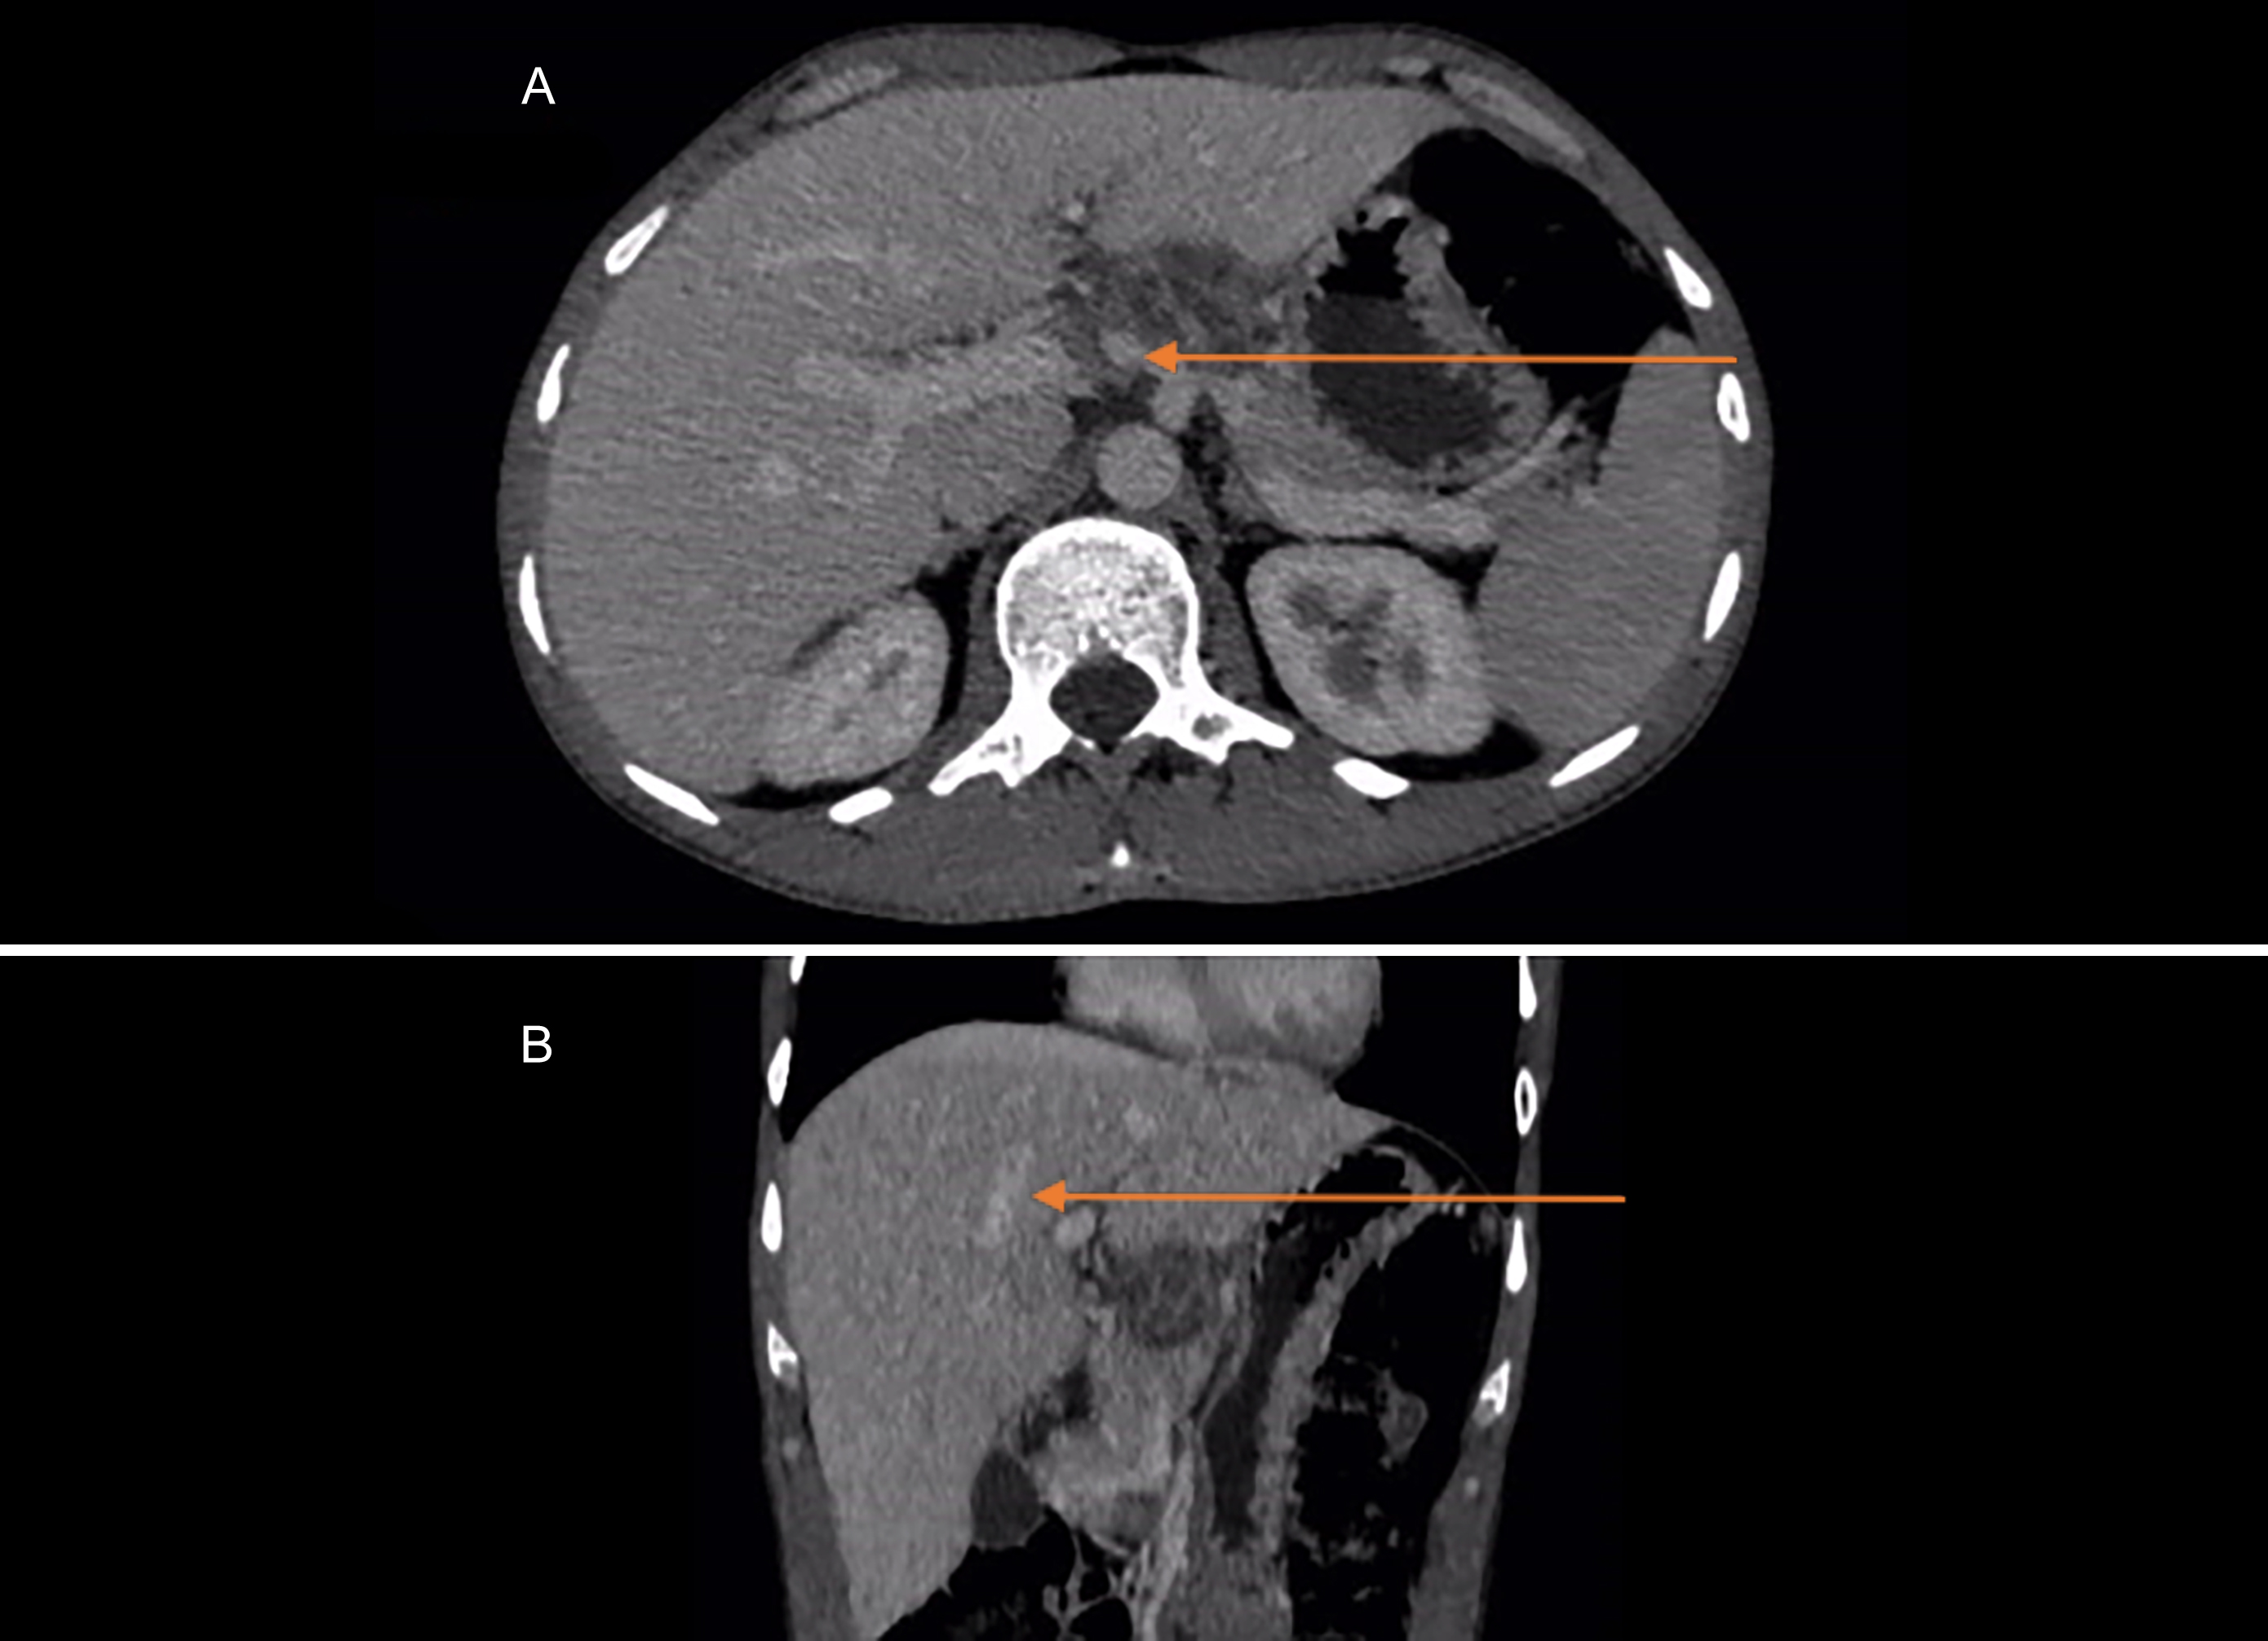

The clinical examination was normal with no visceromegaly or lymphadenopathy. The initial work-up revealed a drop in haemoglobin to 11 g/dl from 15.5 g/dl, reported 3 months before the onset of fever with a normochromic normocytic picture on peripheral smear. Total leucocyte count (TLC) and platelets were in the normal range. Liver function tests, renal profile, and thyroid profile were normal. The blood culture was also negative. However, on ultrasound abdomen, a solid-looking and well-defined mass of 3.5 × 2.3 × 1.7 cm was noted in the head and neck of the pancreas. Abdominal CT scan revealed a multiseptated mixed consistency lesion of 3.5 × 3.1 cm in the pancreatic body projecting in the gastro-hepatic recess, closely abutting adjacent hepatic capsule with marginal neovascularity, and prominent aortocaval necrotic lymph nodes. No visceral metastasis was identified (Figure 1). The patient was listed for an EUS examination. The presence of a heterogenous lesion adjacent to the pancreatic neck was confirmed with no vascular involvement and fine needle aspiration cytology (FNAC) was obtained for diagnosis (Figure 2). Cytology of FNAC sample revealed aggregates of epithelioid histiocytes and few lymphocytes with necrosis suggestive of caseating granuloma. Mycobacterium Tuberculosis was isolated in culture after three weeks. The patient was started on anti-tuberculous medications and his symptoms settled two weeks after starting treatment. He is on regular follow-up in outpatient clinic for compliance and continuation of treatment for one year.

Figure 1: CT scan of abdomen showing a heterogenous mass in the pancreatic body (Arrow) extending into the gastro-hepatic recess in cross-sectional (A), and sagittal sectional view (B).